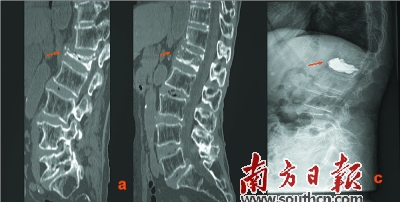

治療前后對比:a為治療前,b為手法復(fù)位后,c為手法復(fù)位+PKP術(shù)后。

梁木榮說:“該患者年紀大、腰椎壓縮程度重,受壓縮的椎節(jié)被壓扁得只剩下1/4,極大地增加了該手術(shù)的難度,很多醫(yī)生都措手無策。”而胡方煜醫(yī)生卻具有豐富的臨床經(jīng)驗,他采取了中西醫(yī)結(jié)合的辦法,先對患病椎體行手法復(fù)位,復(fù)位成功后,再進行PKP手術(shù)。

2012年,連州市人民醫(yī)院康復(fù)醫(yī)學科開始開展這兩項技術(shù),目前該手術(shù)已經(jīng)較成熟,且運用中西醫(yī)結(jié)合的方法,對嚴重的病人術(shù)前進行中醫(yī)手法復(fù)位,使困難的手術(shù)變得簡單,且療效顯著。

對病人先進行中醫(yī)手法復(fù)位,然后再進行PKP手術(shù),術(shù)后再為病人“量身定做”固定支具,是廣東省連州市人民醫(yī)院康復(fù)醫(yī)學科對老年性胸腰椎骨折快速康復(fù)治療常規(guī)的一套方法,針對病情特別嚴重的患者,這種辦法也是經(jīng)常行之有效。

胡方煜介紹:“特別嚴重的患者,椎體壓縮的程度大,椎體后壁不完整,這對手術(shù)有很大挑戰(zhàn),椎體后壁不完整易造成水泥滲漏,手術(shù)具有一定的難度和風險。因此,我科采用中醫(yī)手法復(fù)位、聯(lián)合PKP手術(shù)的方法,先對病人受傷的椎體部位進行手法復(fù)位,椎體牽開整復(fù)后再進行骨水泥注入,使一些重度胸腰椎骨折患者也能完成手術(shù)治療。”